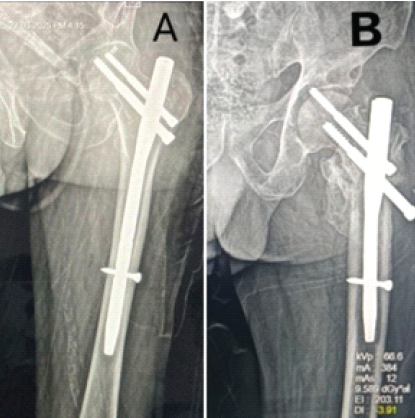

Case 6

A 65-year-old male patient with an operated left pertrochanteric fracture presented 5 months post-operatively with a classical “Z” effect of proximal femoral nail (Fig. 6).

Figure 6: (a) Post-operative anterior-posterior (A-P) view X-ray showing pertrochanteric femur fracture of the left side fixed with a short proximal femoral nail. (b) Post-operative A-P view X-ray showing “Z” effect of proximal femur nail.